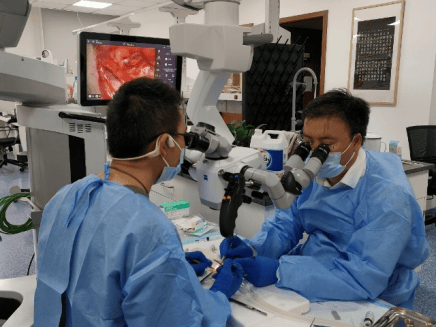

文章展示了手术过程:颈部划出4厘米长的切口,在40-60倍的显微镜下,用比头发丝还细的缝针,将淋巴管和静脉吻合。吻合完毕后,可以看到用荧光标记的淋巴液,流入静脉,不断流动。

现在的LVA手术甚至连操作方式都不统一。丁磊自己参与或者旁观学习了七八场手术,就见证了三种不同做法。最精细的,是吻合淋巴管,“是真正需要水平的”;难度次一级的,是吻合淋巴结,淋巴结比淋巴管大得多,虽然也要用到高倍显微镜,但有经验的医生学起来不算难;更简单的,是吻合淋巴瓣,肉眼就能完成。

任振虎说,LVA指的就是淋巴管静脉吻合术,淋巴结静脉吻合术则叫LnVA,“很多人连这个概念都不清楚”。他估计,全国能做淋巴管吻合手术的医生不超过一百人,而颈部解剖更复杂、淋巴管更细,至少在2025年初,真正有这个技术的医生,“可能不超过20个”。在他看来,今年这项手术已经开始无序扩张了,“卫健委介入得还算及时,否则很难收场”。

任振虎是LVA用于治疗阿尔茨海默症的开创者之一。这和他的主业口腔颌面头颈肿瘤有关。一些患者术后做化疗,会出现淋巴水肿,2021年,他们引入超显微技术来治疗头面部淋巴水肿。任振虎回忆,刚开始还是他自费购买了增倍器,套在医院显微镜下做,后来医院和科室支持,购入了数百万的高倍显微镜。

任振虎和同事在高倍显微镜下做大鼠动物实验。讲述者提供